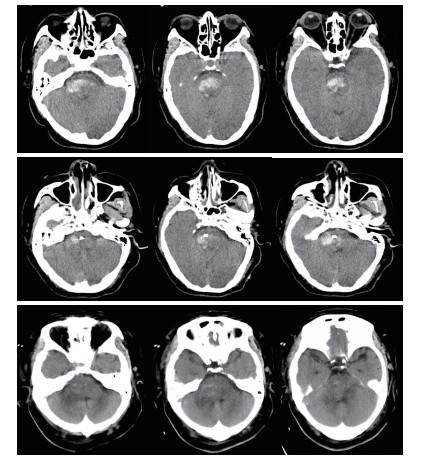

穿刺路径选择:行脑干出血立体定向穿刺分别采用幕上经额部及幕下经桥臂两种入路,笔者根据血肿的位置及患者的病情选择相应的入路,经幕上穿刺尤其适合侵及中脑的血肿,优点:体位摆放方便,对患者呼吸功能影响小,操作较简便,手术时间较短,血压监测较方便。缺点:穿刺路径较长,可能穿过脑室造成引流管移位,穿过丘脑及中脑,损伤损伤丘脑及中脑结构,如引流管置入过深可能损伤延髓。经幕下穿刺优点:经桥臂穿刺,穿刺路径短,损伤重要结构少,缺点:手术中需要侧卧位,可能影响呼吸,手术前应行气管插管,上头架时应预留手术穿刺位置,及耳环的位置,体位摆放及术中操作较复杂,手术时间较长。对于血肿侵及中脑或病情较重的患者,一般选择幕上经额穿刺(图 1)。如患者病情允许或术前有脑积水的患者,一般选择经幕下经桥臂入路,并根据血肿形态使引流管纵行穿过血肿(图 2)。

| 图 1 经幕上入路脑干血肿穿刺A:血肿穿刺前B:血肿穿刺后复查C:穿刺后5 d |

本组手术术后24 h内血肿大部排空有7例,24~48 h大部排空有11例,48~72 h大部排空8例(图 1,2)。于1~4 d内拔除血肿腔引流管。术后8例患者3个月内死亡,死亡率25.8%。1例术中突发血压持续降低后,术后弥漫性脑肿胀死亡。1例术前吸入性肺炎严重,术后感染性休克死亡。1例肝功能不全,术中术后反复出血,家属放弃治疗死亡。1例术后不明原因高热,消化道出血,家属放弃治疗死亡。2例术后突发呼吸心搏骤停死亡。2例术后再出血,家属放弃治疗死亡。18例于术后3个月内清醒,均留有不同程度残疾,5例3个月内未清醒,存活病例随访3个月至1年后,格拉斯哥结局量表(GOS) 5级5例,4级7例,3级6例,2级5例,1级8例。植物状态及死亡患者多为出血量大(>10 mL),术前昏迷程度较深的患者(GCS评分3~5分)。